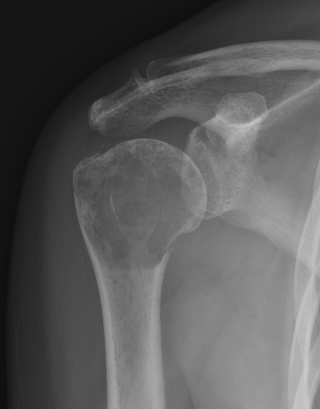

Proximal Humerus

Options

ORIF with plate +/- cement

IMN +/- cement

Tumour prosthesis

Results

Wu et al J Orthop Traumatol 2023

- 45 patients with proximal humerus metastasis

- IM nailing + cement versus plate

- lower blood loss and shorted hospital stay with IMN

- better pain relief with IMN